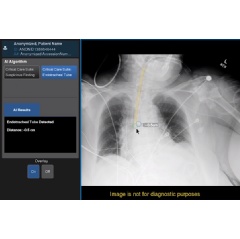

GE Healthcare today announced a new artificial intelligence (AI) algorithm to help clinicians assess Endotracheal Tube (ETT) placements, a necessary and important step when ventilating critically ill COVID-19 patients. The AI solution is one of five included in GE Healthcare’s Critical Care Suite 2.0[2], an industry-first collection of AI algorithms embedded on a mobile x-ray device for automated measurements, case prioritization and quality control.

Up to 45% of ICU patients, including severe COVID-19 cases, receive ETT intubation for ventilation[10],[11],[12]. While proper ETT placement can be difficult, Critical Care Suite 2.0 uses AI to automatically detect ETTs in chest x-ray images and provides an accurate and automated measurement of ETT positioning to clinicians within seconds of image acquisition, right on the monitor of the x-ray system. In 94% of cases the ET Tube tip-to-Carina distance calculation is accurate to within 1.0 cm[13]. With these measurements, clinicians can determine if the ETT is placed correctly or if additional attention is required for proper placement. The AI generated measurements – along with an image overlay – are then made accessible in a picture archiving and communication systems (PACS).